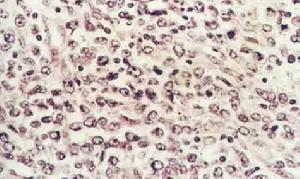

淋巴母細胞1.大細胞淋巴瘤 大細胞淋巴瘤有時也稱硬化性瀰漫性大細胞淋巴瘤,近年來套用表型及基因探針技術追蹤其來源和分化,證單一的大細胞組成。細胞大,胞質豐富,核呈圓形或卵圓形,染色質明顯而分散核仁突出。機化性硬化較少,可能與腫瘤壞死有關。

(1)T細胞免疫母細胞肉瘤:表現出更多的外周T細胞淋巴瘤的特徵。細胞表現為多形性,從體積小核捲曲的淋巴樣細胞到大細胞都有,大細胞胞質豐富,大而分葉的細胞核,核仁明顯。基質富含毛細血管後小靜脈有明顯的細小網狀膠原纖維,機化性硬化雖然不很明顯,見不到濾泡中心細胞淋巴瘤所具有的粗大的互相交錯結合的纖維束。T細胞免疫母細胞肉瘤可表達高分化T細胞抗原,但不表達TdT(早期表現型),這一點與淋巴母細胞瘤正相反

2.淋巴母細胞淋巴瘤 淋巴母細胞是一個沿用了血液學中的習慣用語存在已久的名詞,並沒有表明它在淋巴細胞分化發育中的地位。“淋巴母細胞瘤”的概念也比較混亂,狹義上僅指T細胞的一小部分。“淋巴母細胞瘤”的共同特點如下:①來自“淋巴母細胞”即在成人淋巴組織中沒有相對應的一種細胞,這也是與其他各類淋巴瘤所不同的特點;②瘤細胞皆中等大,胞質少核染色質粉塵樣細,核仁不顯著,核分裂象容易找到,由於瘤細胞的高度轉換率,病變中往往可見“滿天星現象”(腫瘤組織中散在有細胞碎片的巨噬細胞);③常常侵犯末梢血而成為白血病。